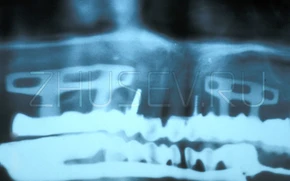

А эти имплантаты-гвоздики молотком забивались в челюсть в любых местах и под любым углом.

Вариация на тему цилиндрического имплантата с канавками, в которые должна была врастать кость.